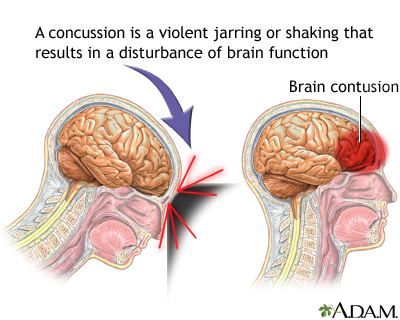

- Concussion, most often in which the brain has been shaken, is the most common type of traumatic brain injury.

Symptoms of a head injury can occur right away or may develop slowly over several hours or days. Even if the skull is not fractured, the brain can hit the inside of the skull and be bruised. The head may look fine, but problems could result from bleeding or swelling inside the skull.

Some head injuries cause changes in brain function. This is called a traumatic brain injury. A concussion is a type of traumatic brain injury. Symptoms of a concussion can range from mild to severe.